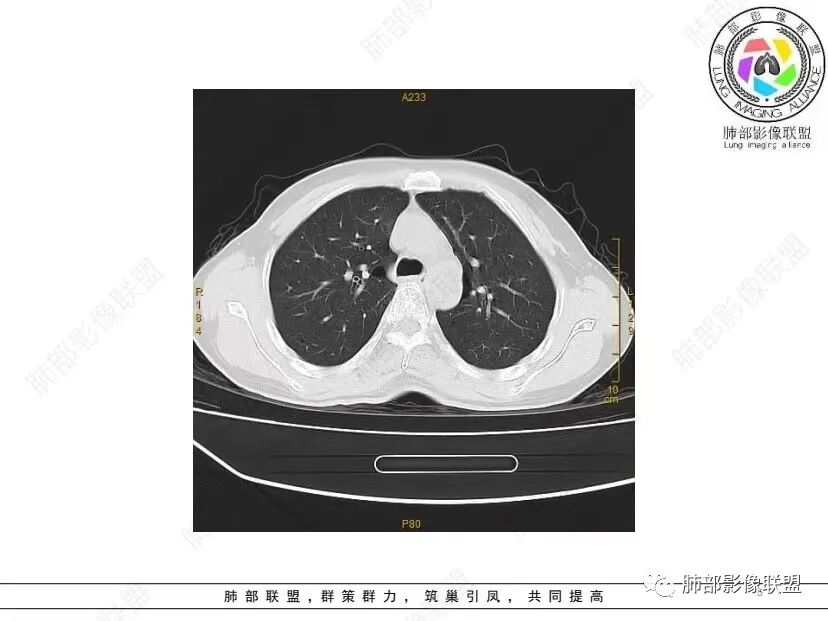

秦化君: 晨读 双肺不均匀散在多发囊状影,大小不等,部分囊形态欠规整,壁薄均匀,部分囊胸膜下平行。双肺少许斑片状磨玻璃影,边缘模糊。考虑BHD综合征。鉴别PCP,LIP。

红日初升: 中年女性,双肺多发气囊,背景干净,大小不一,下肺韧带旁较大,考虑BHD,鉴别LIP、LAM

宇宙: 中年女性,两肺多发大小不等薄壁囊状影,两肺纵膈胸膜下分布明显,考虑BHD,鉴别LAM

这个病例目前影像特点,多囊,囊主要位于下肺,胸膜下及小叶核心为主

伴随少许索条,而且这些病灶与囊不一定有相关性

囊的分布,PLCH基本可以排除

囊壁薄且均匀,光滑,形态规则,基本除外恶性

单纯囊,无斑片及其他实性病灶,感染不支持,可能的是:LAM、BHD、LIP

从囊的分布、大小,BHD可能性可能大一些,但是LIP、LAM都可以这样表现,具体诊断应该是这三种之一,影像缩小到这里我觉得就差不多了,结合临床考虑就行,不支持靠影像强下结论。